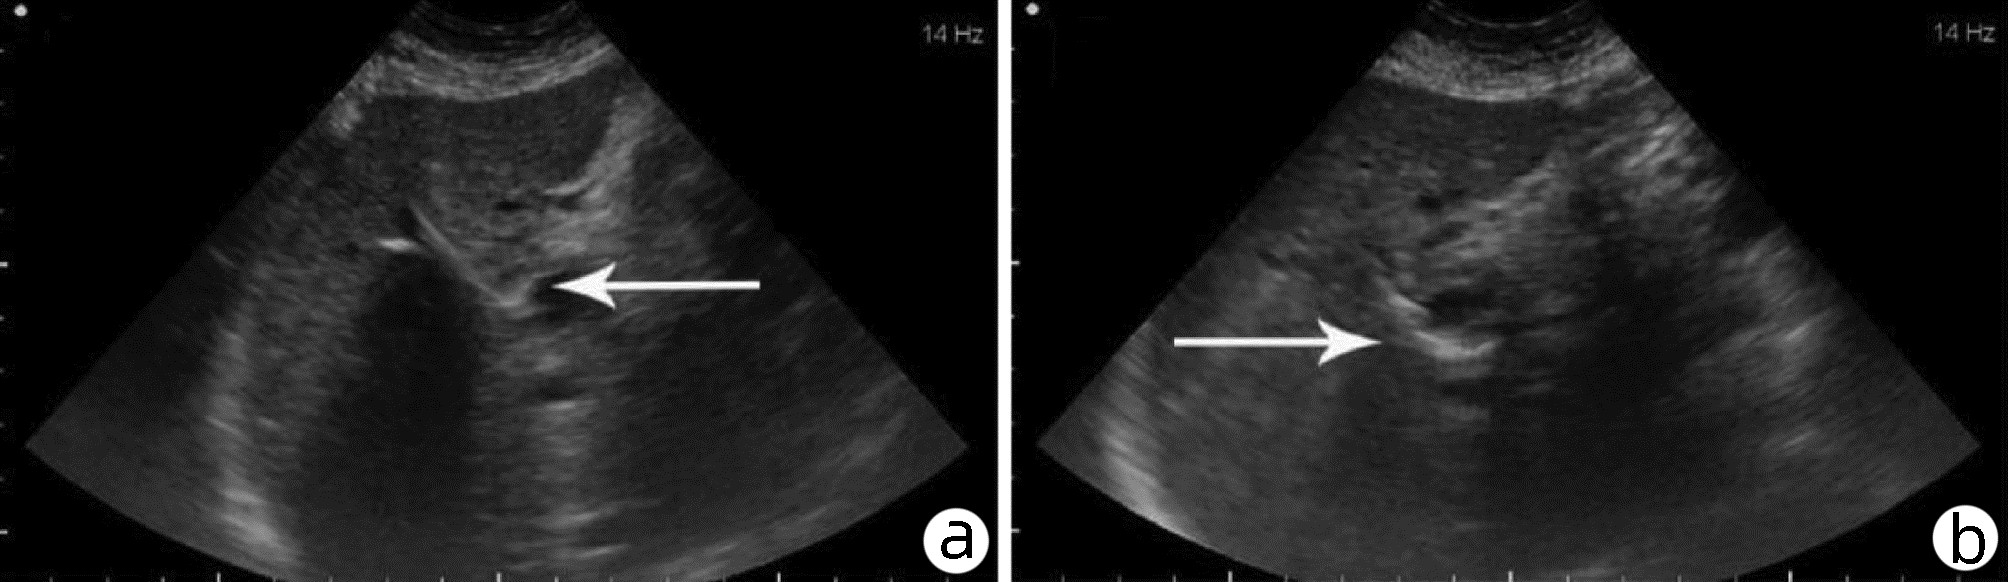

Application and clinical evaluation of ultrasound-guided biliary drainage tube replacement technology

Anhong ZHANG, Ruixin ZHANG, jie MA, Bo QIU, Xin YI, Zhihua LU, Lijie ZHENG, Hanguang DONG, Tian HAN, Li ZHANG, Yuanhui JIANG, Jun XU

2022, 38(11): 2542-2545. DOI: 10.3969/j.issn.1001-5256.2022.11.020

Abstract(1275) HTML (362) PDF (1987KB)(37)

Abstract:

Objective  To summarize the preliminary application results of ultrasound-guided biliary drainage tube replacement, present the corresponding technical points, and discuss the operation strategy and clinical application value.  Methods  The clinical data of 60 patients who underwent ultrasound-guided biliary drainage tube replacement in Qilu Hospital of Shandong University between August 2014 and August 2020 were retrospectively analyzed. The operation procedure, clinical applications, and postoperative complications were summarized and analyzed.  Results  Fifty-eight of the 60 patients (96.67%) were successfully replaced with drainage tubes along the original sinus. Among them, dilated sinus tracts of 47 patients were placed with coarse-grade drainage tubes, and dilated sinus tracts of the remaining 11 patients were placed with the original type of drainage tubes, with the mean operation time of 15.8(12.0-19.0) min under local anesthesia. In total, bile was drained from 28 patients receiving PTCD drainage, 23 patients receiving gallbladder drainage, and 9 patients receiving T-tube drainage. The post-operation evaluation revealed that the drainage situation has improved, with a 100% effective rate. No obvious abnormality was found in the postoperative follow-up visit.  Conclusion  The replacement of drainage tube under ultrasound guidance is simple, safe and feasible, and it provides further promotion in clinical practice with sufficient data support.